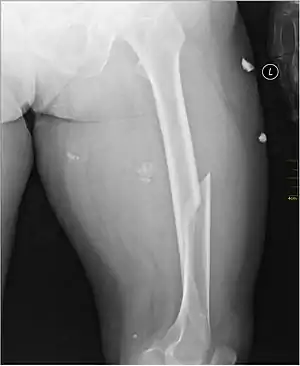

شکستگی ران

شکستگی ران شکستگی استخوان است که در استخوان ران رخ میدهد. به دلیل نیروی زیادی که برای شکستن استخوان لازم است، این رخداد معمولاً در ترومای با ضربه زیاد مانند تصادفات اتومبیل روی میدهند. شکستگی تنه استخوان یا میانه استخوان ران متفاوت از سر، گردن و تروکانتر است.

| X-ray image of a femoral shaft fracture | |

شکستگی معمولاً واضح است، زیرا شکستگی استخوان ران اغلب ناشی از ضربهای با انرژی بالا است.[1] علائم شکستگی شامل تورم، تغییر شکل و کوتاه شدن پا است. آسیب بافت نرم، خونریزی و شوک گسترده است. شایعترین علامت درد شدید است که از حرکت پا جلوگیری می کند.